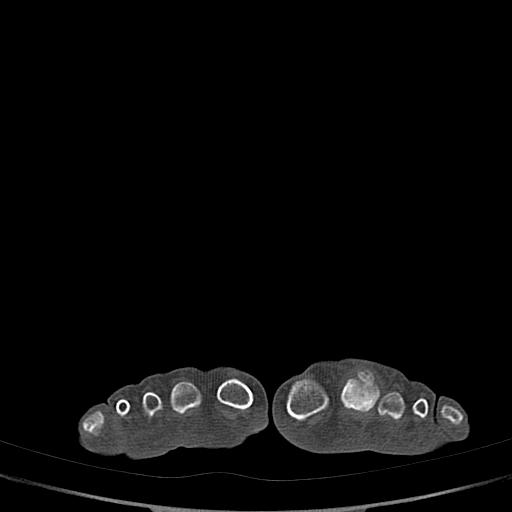

男72岁左侧跖趾关节肿痛15年,查压痛。

骨软骨瘤可能性大,请上传x光片.

不象软骨瘤,

考虑退行性骨关节病。